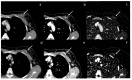

Dual-energy computed tomography (DECT) is one of the most promising technological innovations made in the field of imaging in recent years. Thanks to its ability to provide quantitative and reproducible data, and to improve radiologists' confidence, especially in the less experienced, its applications are increasing in number and variety. In thoracic diseases, DECT is able to provide well-known benefits, although many recent articles have sought to investigate new perspectives. This narrative review aims to provide the reader with an overview of the applications and advantages of DECT in thoracic diseases, focusing on the most recent innovations. The research process was conducted on the databases of Pubmed and Cochrane. The article is organized according to the anatomical district: the review will focus on pleural, lung parenchymal, breast, mediastinal, lymph nodes, vascular and skeletal applications of DECT. In conclusion, considering the new potential applications and the evidence reported in the latest papers, DECT is progressively entering the daily practice of radiologists, and by reading this simple narrative review, every radiologist will know the state of the art of DECT in thoracic diseases.